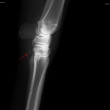

Čip ve spěnkovém kloubu na pánevní končetině

Ankylóza spěnkovýho kloubu